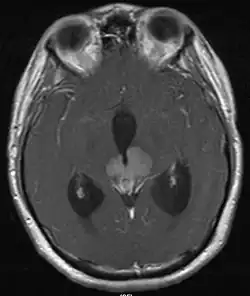

• Mainly located in midline structures, suprasellar region or pineal gland, also basal ganglia and hypothalamus

Location